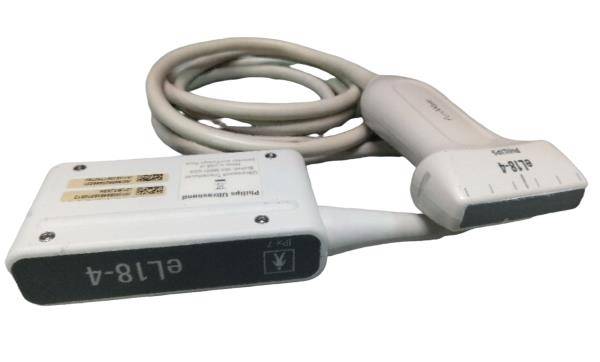

Acquire a trusted healthcare companion with our Philips IU22 3D/4D Ultrasound System, now available for purchase. This pre-owned model, possessing a legacy of reliability, is being offered in an excellent operational condition and comes with a complete set of four probes.

Comprehensive Functionality: Despite showing minimal signs of cosmetic wear, the unit remains fully functional and geared for immediate clinical deployment. All probes have been diligently tested to ensure optimal performance. Extensive care has been taken to maintain the system, reaffirming its condition akin to new.